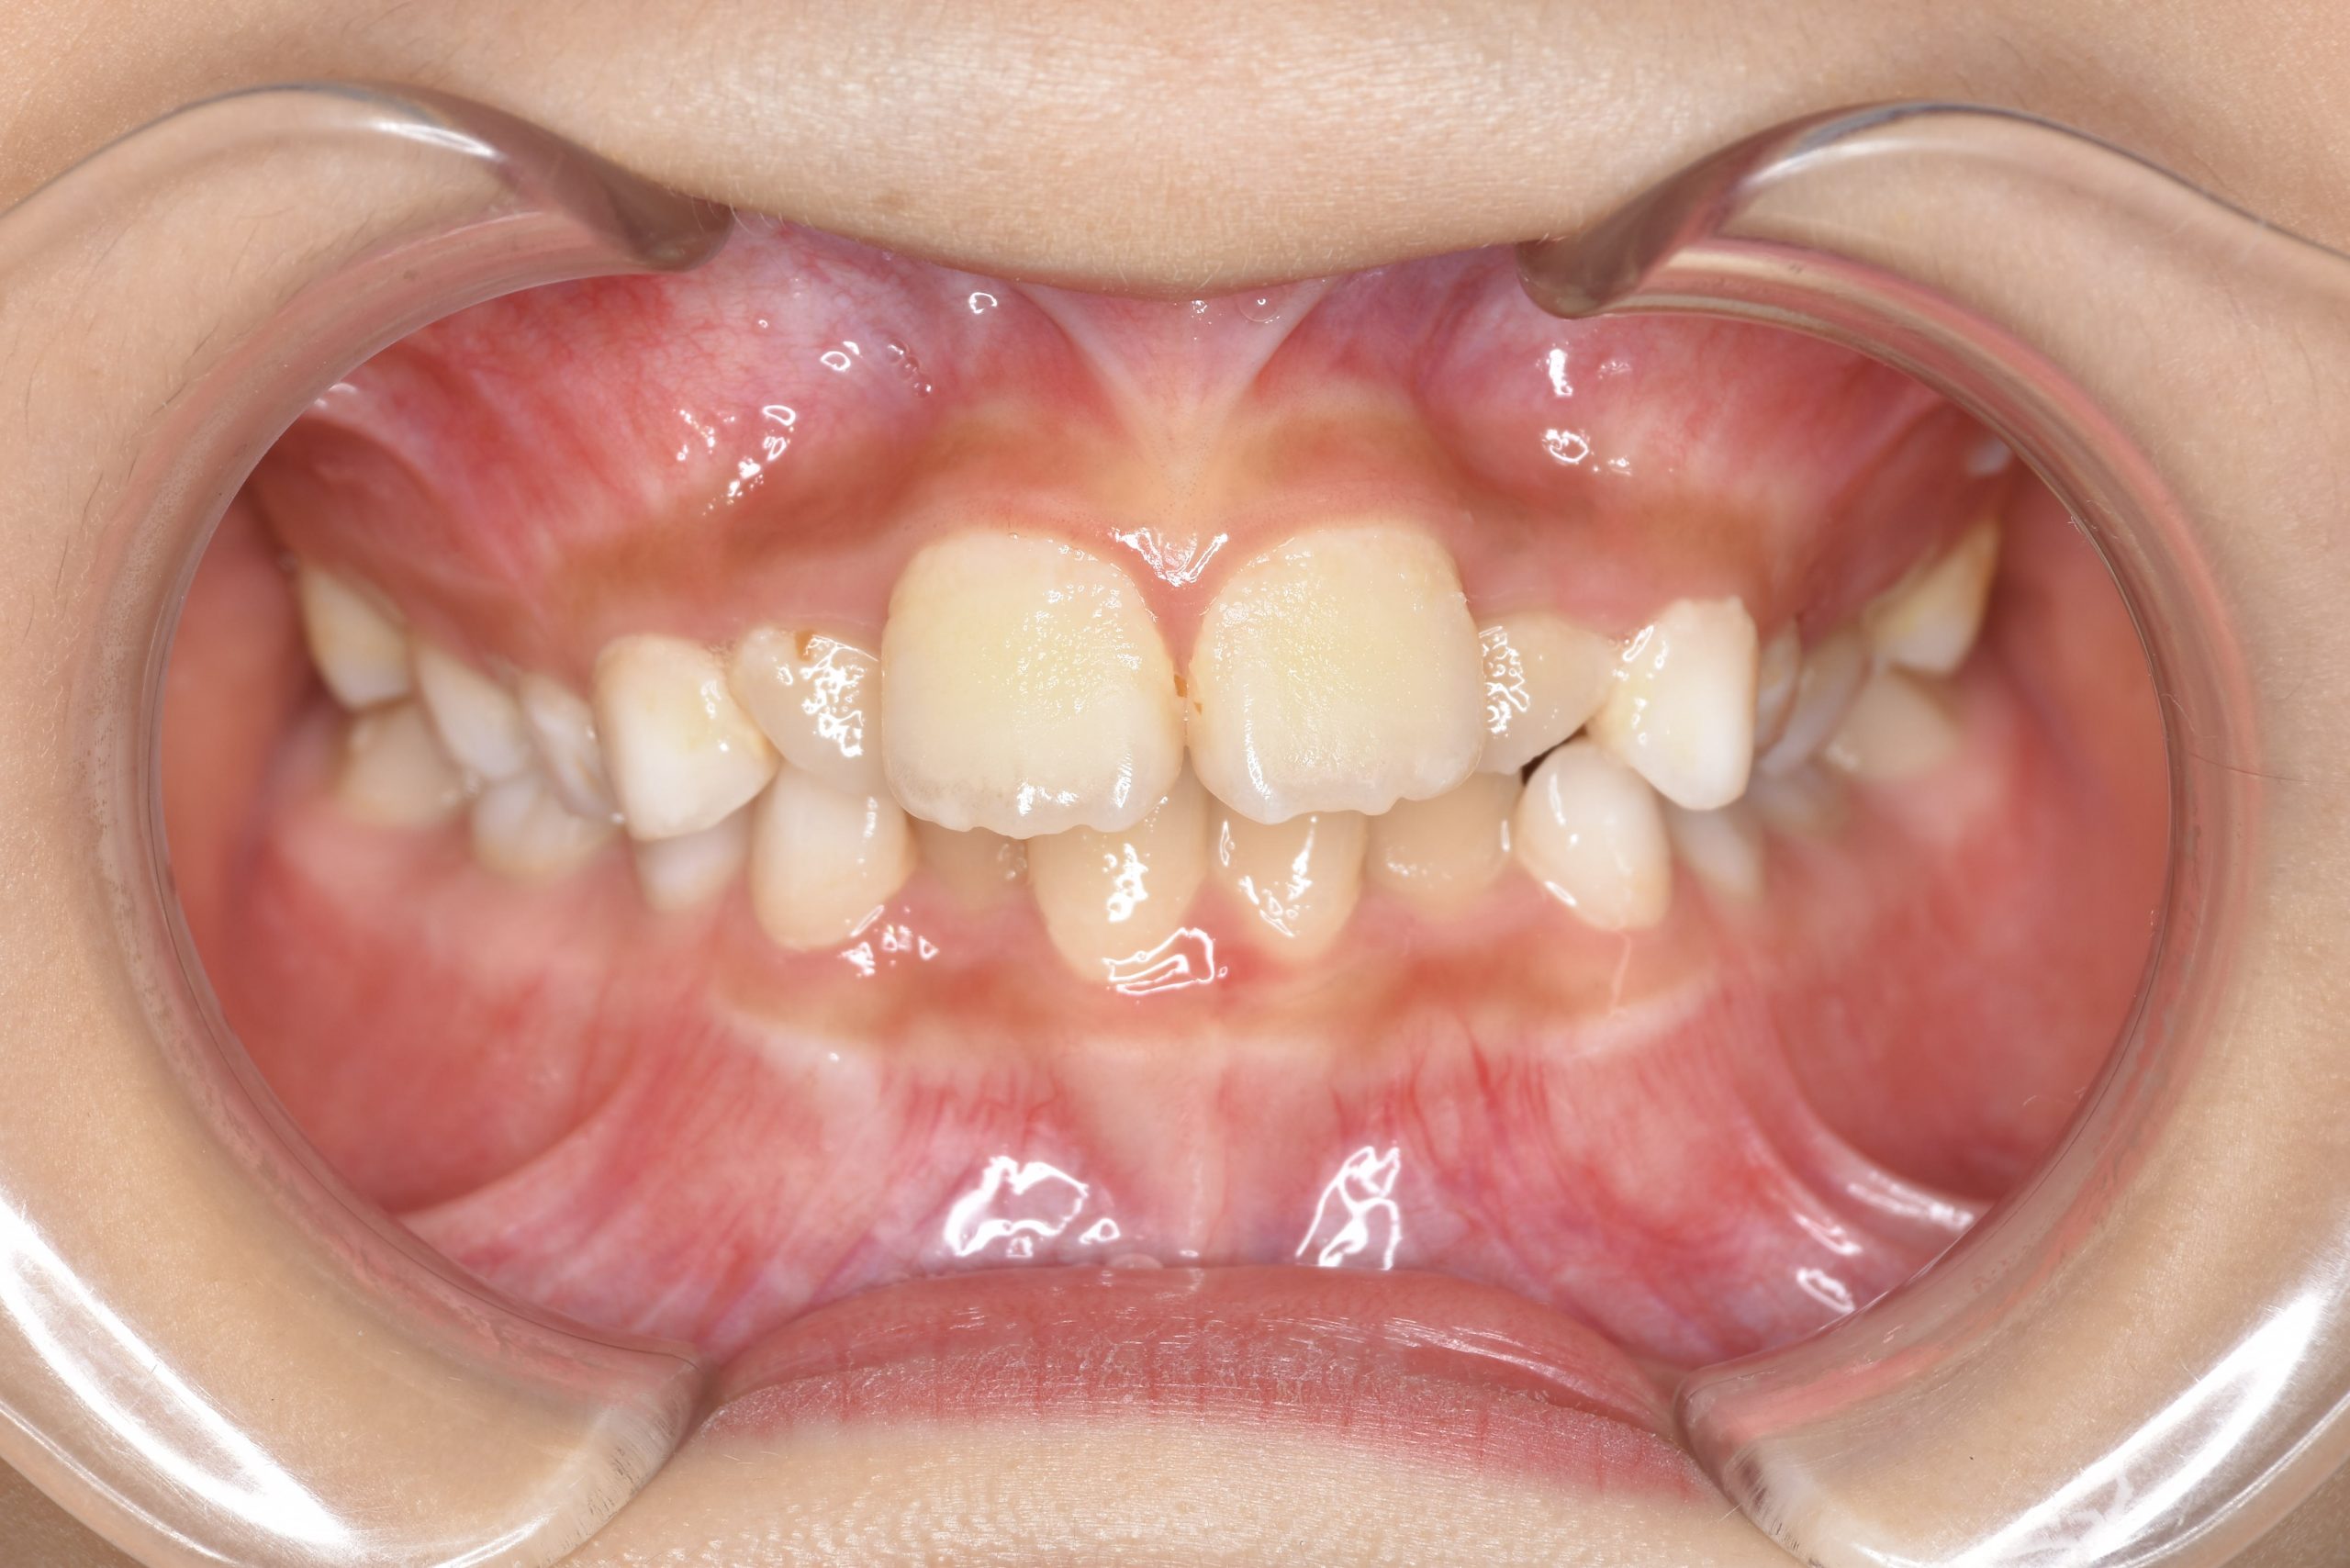

ビフォー

全顎ワイヤー矯正 症例_185

主訴 歯並び|横から生えている大人の歯

施術内容 小児矯正1期治療

治癒期間 4年間

費用 522,960円(税込)